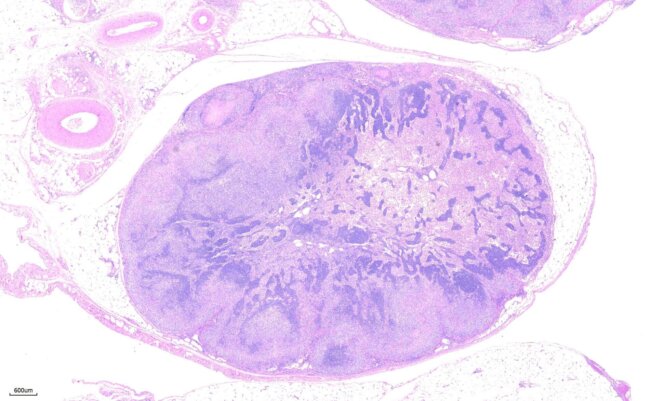

動物外科病理-腫瘤淋巴結轉移

腫瘤轉移-腎臟 Tumor renal metastases